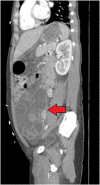

Female with peritonitis and abdominal distention